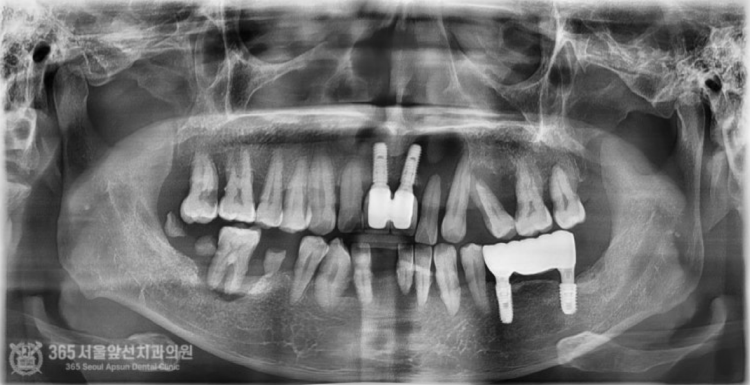

안녕하세요. 도화역치과 365서울앞선치과입니다. 오늘 소개해 드릴 치료 증례는 지인분의 소개로 찾아오셨던 환자분이십니다. 전체적으로 치아가 좋지 않으나 일단 아랫턱부터 치료를 완료하고 나서 윗턱을 치료받고 싶다고 하셨습니다. 바쁘게 사회생활을 하셔야 하는 환자분이셔서 발치와 동시에 뼈이식을 진행하며 임시치아까지 즉시 만들어 드렸습니다 ㅎㅎ 촬영일시: 2024.06.20. 처음 도화역치과 365서울앞선치과에 내원하셨을 당시 엑스레이 사진입니다. 전체적으로 잇몸뼈 소실 증상이 있고 치아 상태가 매우 좋지 않습니다. 일단 위쪽은 아래쪽 치료를 마무리 한 이후에 하기로 결정하셨습니다. 촬영일시: 2024.07.06. 발치와 동시에 뼈이식을 진행하면서 임플란트 식립까지 완료한 이후 엑스레이 사진입니다. 가지런히 식립된 임플란트 보기 좋습니다 ㅎㅎ 수술시간은 대략 30분 정도 걸렸습니다.